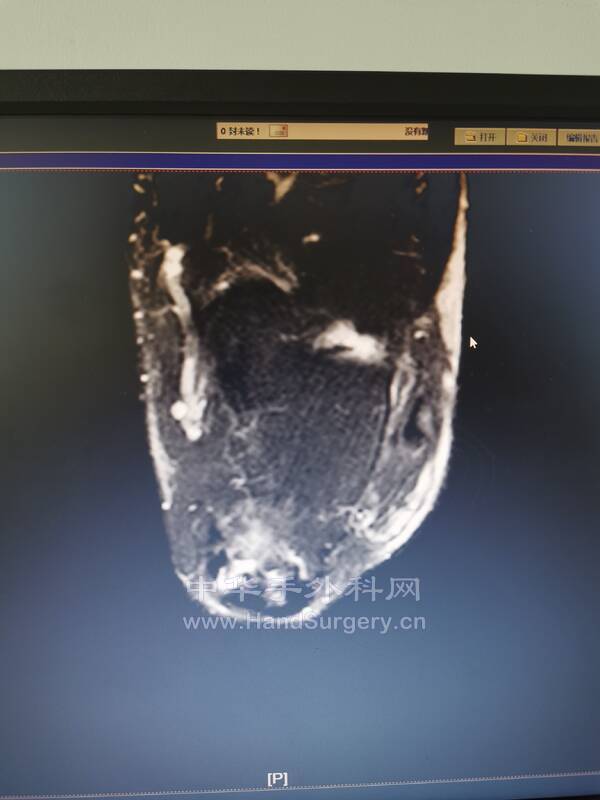

比如这个患者

跟腱止点断裂

再看核磁影像,手术所见历历在目